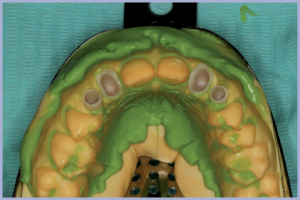

- Fig. 25 – Impronta di posizione delle cappette in zirconia

I successivi passaggi portavano all’allestimento dei manufatti definitivi in zirconia-ceramica. In particolare venivano allestite tramite procedura CAD-CAM delle cappette in zirconia da incollare sui monconi per ottenerne una individualizzazione estetica; sempre con procedura CAD-CAM si ottenevano le strutture in zirconia successivamente ceramizzate per ottenere i manufatti definitivi (Figg. 23-25).

A distanza di 3 mesi dal posizionamento implantare si procedeva alla rimozione dei manufatti provvisori (monconi temporanei con relativa corona e corone provvisorie a livello degli incisivi laterali) ed alla rilevazione di una impronta degli impianti e dei monconi naturali (Figg. 21-22).

- Figg. 23a, b – Monconi customizzati e cappette in zirconia pronti per la prova

- Figg. 24a, b – Particolari delle cappette e dei monconi customizzati